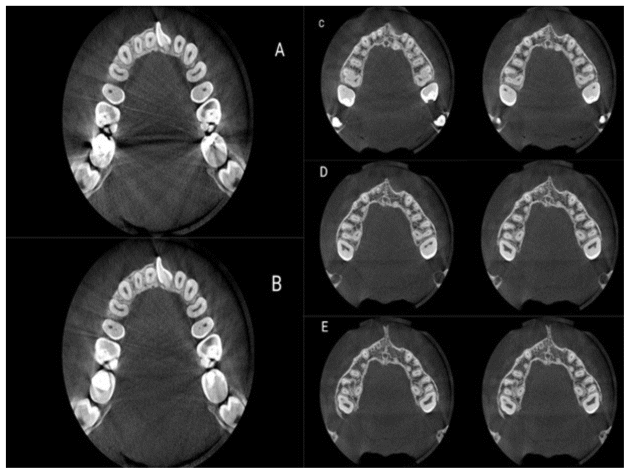

A total of 41 CBCT scans (132 maxillary first and second molars) were evaluated. All CBCT scans were obtained with the ProMax 3D CBCT scanner (Planmeca, Helsinki, Finland) using a voxel size of 0.15 × 0.15 mm, a tube potential of 84 kV, and a tube current of 9 mA. The images were saved, and the MAR algorithm with medium intensity was applied to them in Romexis version 3.8.0 software; this series of images was also saved. The images were then randomly coded, and two endodontists were asked to evaluate them for the presence/absence of MB2 in the maxillary first and second molars, based on the position of the first mesiobuccal canal (MB1). In the presence of MB1 at the center of the mesiobuccal root, the possibility of MB2 would be excluded, and the tooth would be excluded from the study (Campo (4) Figure 1).

The two endodontists also evaluated the visibility of MB2 in maxillary first and second molars on each CBCT image in the apical, middle, and coronal thirds according to the presence/absence of restoration or presence of an artifact-generating factor in the respective tooth or adjacent teeth, and also presence/absence of root filling in the respective tooth or adjacent teeth (Figure 2). The observers used all CBCT sections (axial, sagittal, and coronal) for their assessments. In the event of a disagreement between the two observers, a radiologist would be consulted. The observers reported the visibility of MB2 using a 5-point Likert scale as follows, (10):